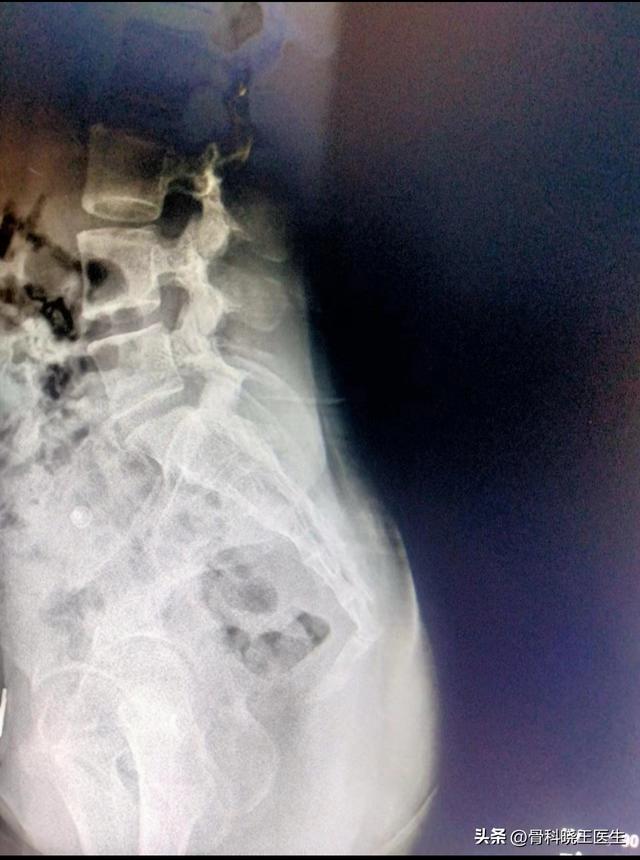

尾骨在脊柱的最末端,是代表尾巴的退化器官,由3至5块尾椎融合后形成,在上面与骶骨形成关节。

正如前文所述,由于尾骨处于脊柱的最尾端,是人体进化退变后的结构,因此骨折后除了疼痛,一般没有明显的后遗症。但是如果骨折后尾骨尖端向内侧移位明显,可能会刺激直肠,导致排便困难,另外有很少部分人尾骨骨折后可能会出现局部顽固性的疼痛。

尾骨骨折并不会影响骨盆的稳定,骨折后产生的疼痛一般经3-4周后的休息就会好转,因此一般不需要手术,若骨折移位较明显,早期可以采取经肛门手法复位的方法。但是若尾骨骨折导致直肠压迫、刺激或损伤,或者存在顽固性疼痛,可能需要手术切除尾骨。